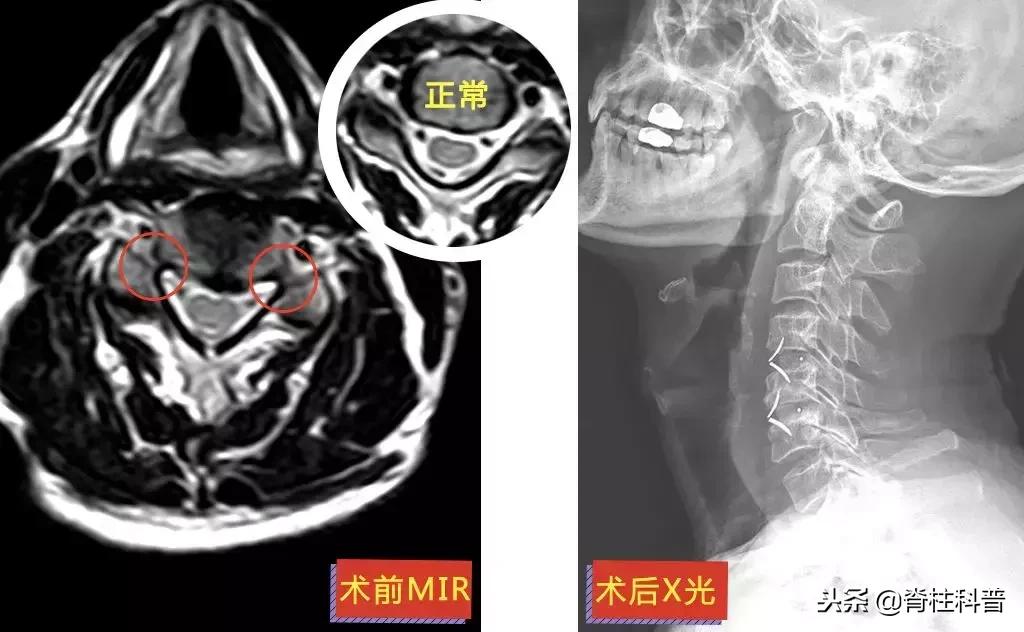

另一位方大爷,3年前(2015年)出现双下肢麻木疼痛,以双大腿、小腿后侧明显,活动时麻木疼痛症状加重。还有双下肢乏力、酸痛感、足踩棉花感。

2年前(2016年)出现右上肢麻木感,以右手绕侧(拇指一侧)、拇指、示指、中指及环指明显,伴有右手精细活动受限。予以针灸、物理治疗等对症保守治疗,效果不佳。上述症状逐渐加重。2个月余前(约2018年5月),最长行走距离为100米时出现双下肢麻木疼痛感。

▲ 方大爷:脊髓型颈椎病